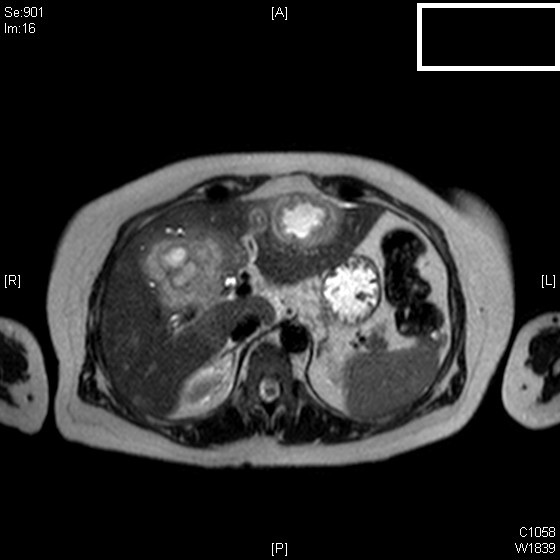

Presentamos el caso de una mujer de mediana edad con antecedentes de colecistectomía y varios episodios de coledocolitiasis residual resueltos endoscópicamente. Acude al servicio de Urgencias por un nuevo cuadro de dolor abdominal y alteración de enzimas hepáticas, apreciándose en las pruebas de imagen lesiones sugestivas de abscesos hepáticos sin poder descartarse un origen maligno. Dada esta duda se decide realizar una biopsia con aguja gruesa llegando al diagnóstico de pseudotumor inflamatorio hepático relacionada con la enfermedad por IgG4. Ésta es una entidad infrecuente pero que debe ser tenida en cuenta debido a que, a diferencia de la patología maligna, que es el principal diagnóstico diferencial, su comportamiento es benigno, con buena evolución con tratamiento médico. Por ello es vital un adecuado diagnóstico para evitar procedimientos diagnóstico-terapéuticos agresivos.